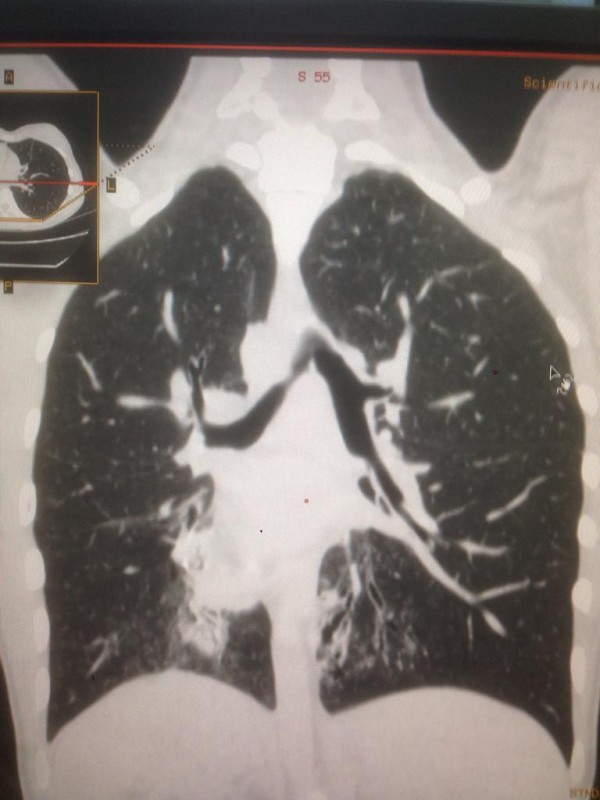

Синдром Зиверта-Картагенера. Снимок предоставлен Сундетом Саргеловым

Также зеркальное расположение внутренних органов встречается при синдроме Зиверта-Картагенера, это аутосомно-рецессивное генетическое заболевание. Его коэффициент один случай из 50 тысяч человек. В настоящее время в Казахстане на учете с такой патологией состоят 16 детей.

"Это генное нарушение. При нем у людей нездоровы дыхательные пути. Характерные черты: синклиты, бронхоэктазы и зеркальное расположение органов. Люди с таким диагнозом испытывают слабость, температуру, боль в ушах, одышку, хрипы. Поэтому пациенты с раннего возраста проходят лечение. Состоят на диспансерном учете у детского пульмонолога. В год они получают около пяти раз стационарное лечение, находятся под наблюдением врачей, пропивают антибиотики", - говорит собеседник.